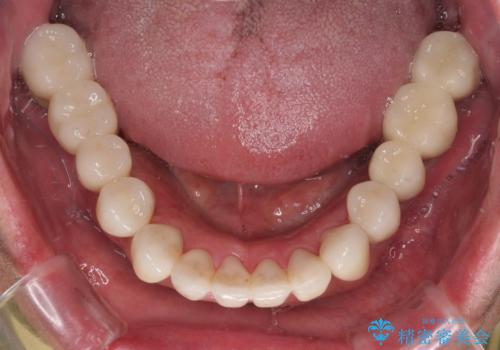

前歯部の審美面も大幅に改善され、大変満足していただけました。